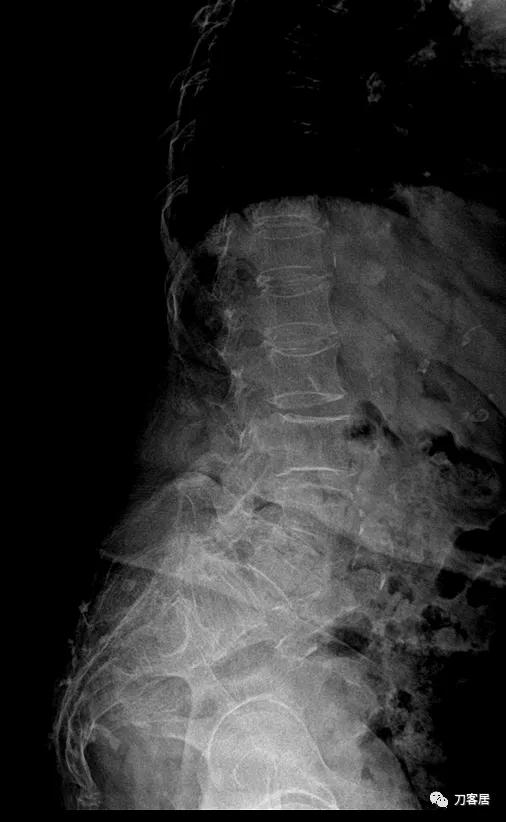

@胡满 如果是我的话,对于这种病例,首先抗骨质疏松治疗半年后再看情况,而且如果患者经济条件可以的话,建议直接使用特立帕肽,因为从患者的X线片来看,骨质疏松严重。患者的腰5滑脱应该是真性滑脱,腰5有峡部裂,腰4滑脱是退变滑脱,腰4-骶1椎管狭窄。但患者的痛苦不一定是椎管狭窄引起的。即使是做手术,患者的骨密度太低,钉子把持力不够。所以,先正规抗骨质疏松半年后再说手术吧。

患者为69岁,女性, 就诊日期:2021年11月8日。因晨起腰痛2天,就诊当日有缓解。疼痛自腰部放射至大腿后侧。2004-2005年曾有腰椎骨折病史,保守治疗后愈。

腰椎X线片提示腰5峡部裂,腰5椎体前滑脱1度,膝关节X线片提示退变增生,右侧髌股关节增生、狭窄、骨刺形成。骨密度提示骨质疏松,T值最低-3.3。2014年曾换心脏瓣膜手术,长期服用华法林,辅酶Q10, 盐酸曲美他嗪。

诊断:骨质疏松症,腰5峡部裂,腰5椎体前滑脱1度,双膝关节创伤性关节炎。